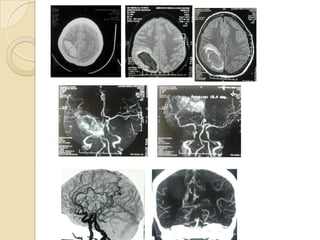

Multiple aneurysms in a 54-year-old woman.

CT-angiography vs MR-angiography:

Characteristics CT-angiography MR-angiography

Spatial resolution Good Fair

Size of vessel upto 0.6mm 1.0-1.5mm

Tortuous vessel better visualized -

Time seconds minutes

Risk of radiation exposure yes no

Use of contrast always +/-

Detection of calcification excellent -

ferromagnetic substance indicated not indicated